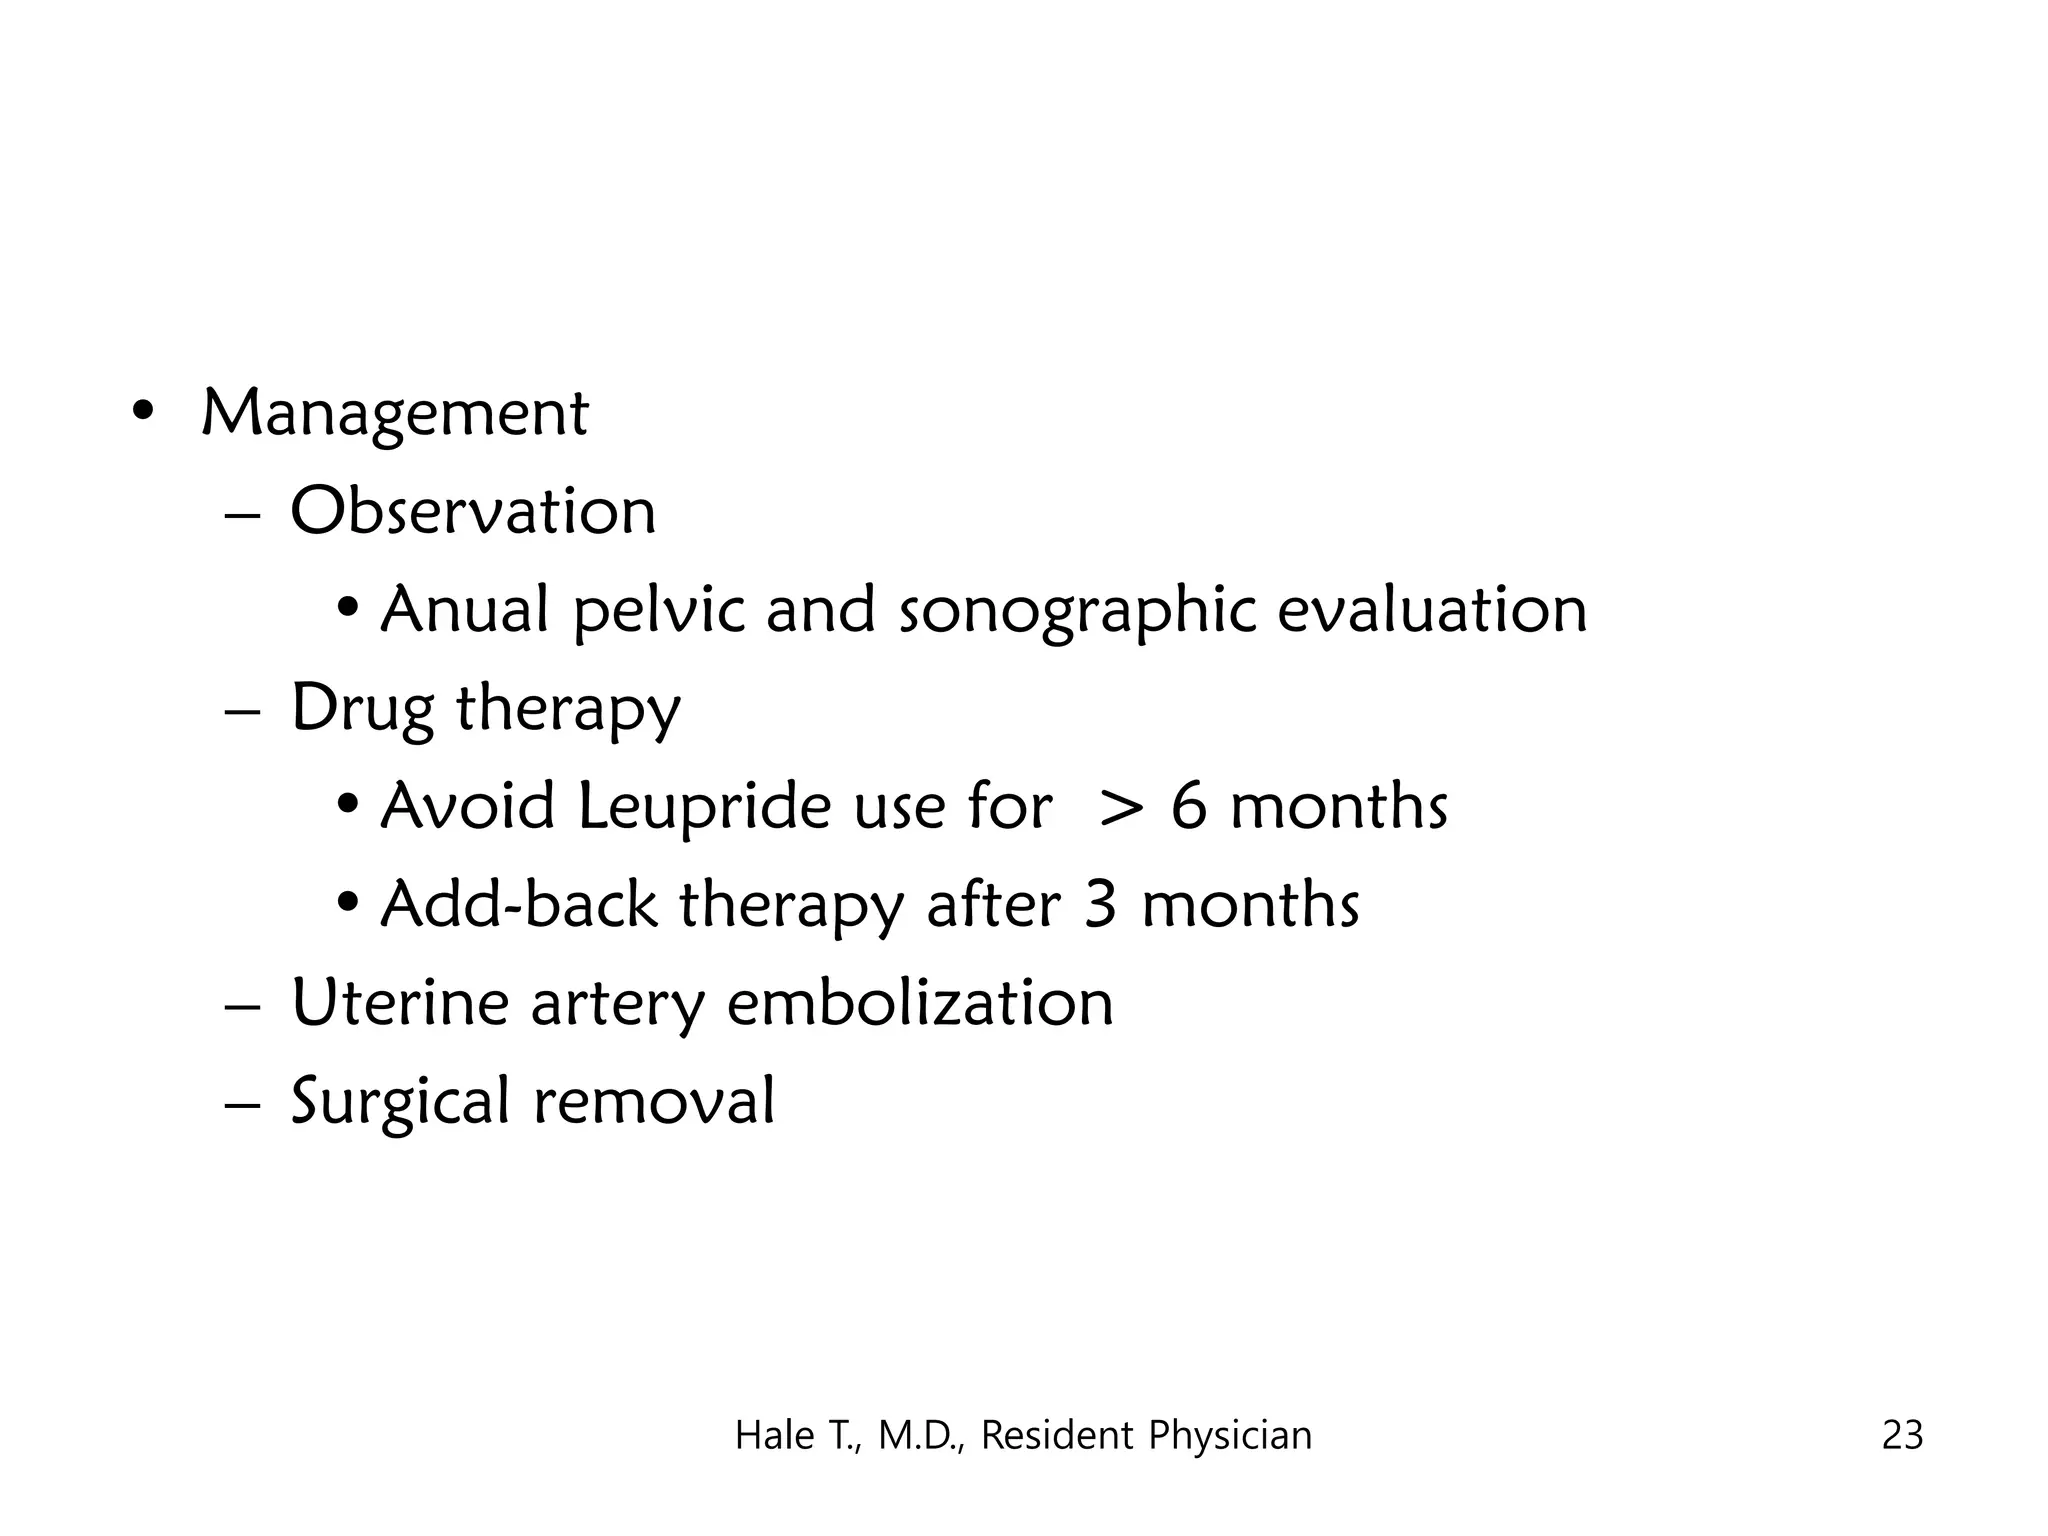

This document discusses myomas (uterine fibroids). It notes that myomas are benign smooth muscle tumors that originate in the uterus and are sensitive to estrogen and progesterone. Symptoms can include bleeding, pain, pressure, and infertility. Diagnosis is usually made through imaging like ultrasound or MRI. Treatment options include observation, drug therapy, uterine artery embolization, or surgical removal of the fibroids. The document also discusses complications that can arise if fibroids are present during pregnancy, such as pain, bleeding, preterm birth, and pregnancy loss.